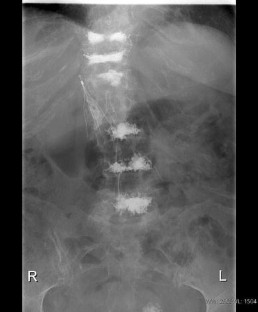

Retrieval of Cement Embolus from Inferior Vena Cava After Percutaneous Vertebroplasty

Percutaneous vertebroplasty is an accepted treatment for painful vertebral compression fractures caused by osteoporosis and malignant disease. Venous leakage of cement and pulmonary cement embolism have been reported complications. We describe a paravertebral venous cement leak resulting in the deposition of a cement cast in the inferior vena cava and successful retrieval of the cement embolus.

Fig. 2